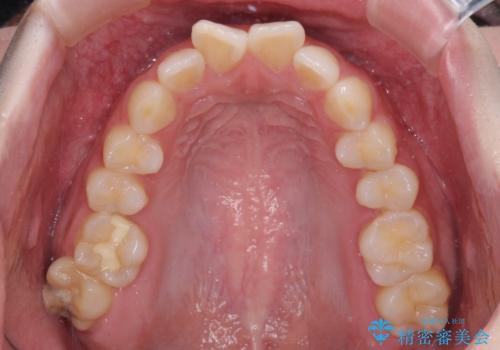

前歯のデコボコをインビザラインできれいに整える

- 前歯のデコボコと上下の隙間を気にして来院された患者様です。

前歯の捻れを改善するとともに、口元が少しでも引っ込むように治療計画を立て、仕上げることができました。